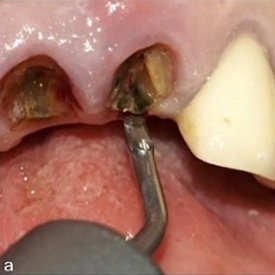

Dr. Rosas: W&H offers very fine instrument tips (editor’s note: e.g., EX1 & EX2) with a diameter of only 0.2 mm. These allow precise entry into the periodontal ligament space, enabling controlled luxation of the tooth. With appropriate clinical skill, this significantly simplifies the extraction procedure. In particular, piezoelectric technology facilitates rapid and efficient extractions of severely ankylosed teeth in older patients or teeth with long-standing endodontic treatment. The specialised instrument geometry also allows for precise odontosections. In this way, atraumatic extraction becomes a safe and predictable procedure.

Figure 2: Syndesmotomy using the piezoelectric periotome (EX1 by W&H) (a), positioned in the periodontal ligament space at the level of the palatal fragments (b).